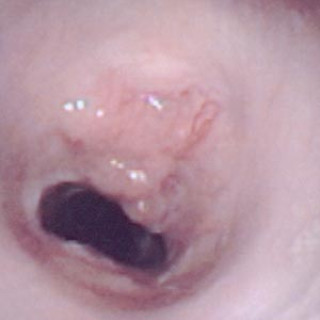

Myiasis (av gresk «myia», flue) foreligger når mennesker eller dyr angripes av fluelarver som ernærer seg på levende eller dødt kroppsvev. En rekke fluearter kan forårsake myiasis i hud, nasopharynx, øyne og gastrointestinal- eller urogenitaltractus (1). Den kutane form er langt den vanligste. I Norge er disse tilstandene sjeldne, men med økende reiseaktivitet vil vi av og til møte pasienter med sykdommen. Pasienten. En 43 år gammel norsk mann fikk under en to ukers reise i Amazonas, Brasil, tre «flåttbitt» på henholdsvis underekstremiteter og på halsen. Bittene på underekstremitetene tilhelet...